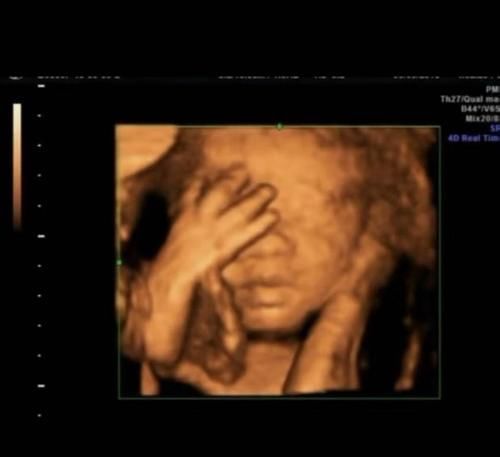

当受精卵缓慢发育成胎儿时,神经和各种器官发育缓慢。因此,当胎儿是第一个人类时,它已经有睡眠,但是在早期阶段,睡眠时间更长,这时胎儿需要的睡眠越来越少,此时胎儿的运动会越来越频繁。